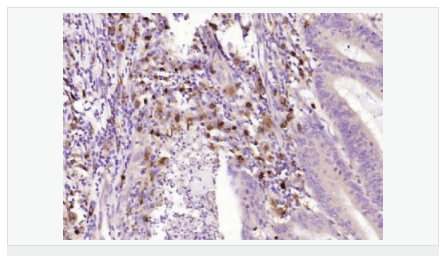

交叉反應(yīng):Human,Mouse,Rat(predicted:Pig,Horse,Rabbit) 推薦應(yīng)用:WB,IHC-P,IHC-F,ICC,IF,ELISA

產(chǎn)品應(yīng)用WB=1:500-2000 ELISA=1:5000-10000 IHC-P=1:100-500 IHC-F=1:100-500 ICC=1:100-500 IF=1:100-500 (石蠟切片需做抗原修復(fù))